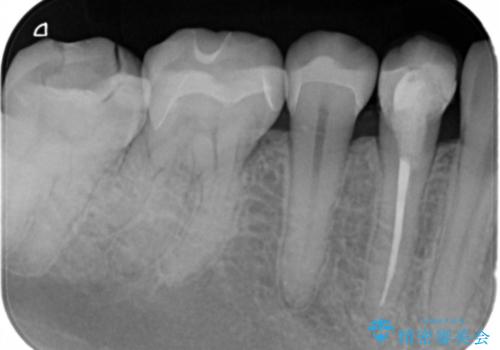

- 口を開けた時、銀の詰め物が目立つとのことで来院。

拡大鏡下で詰め物を外し、う蝕がない事を確認して、セラミック(e-maxインレー)で治療を行いました。